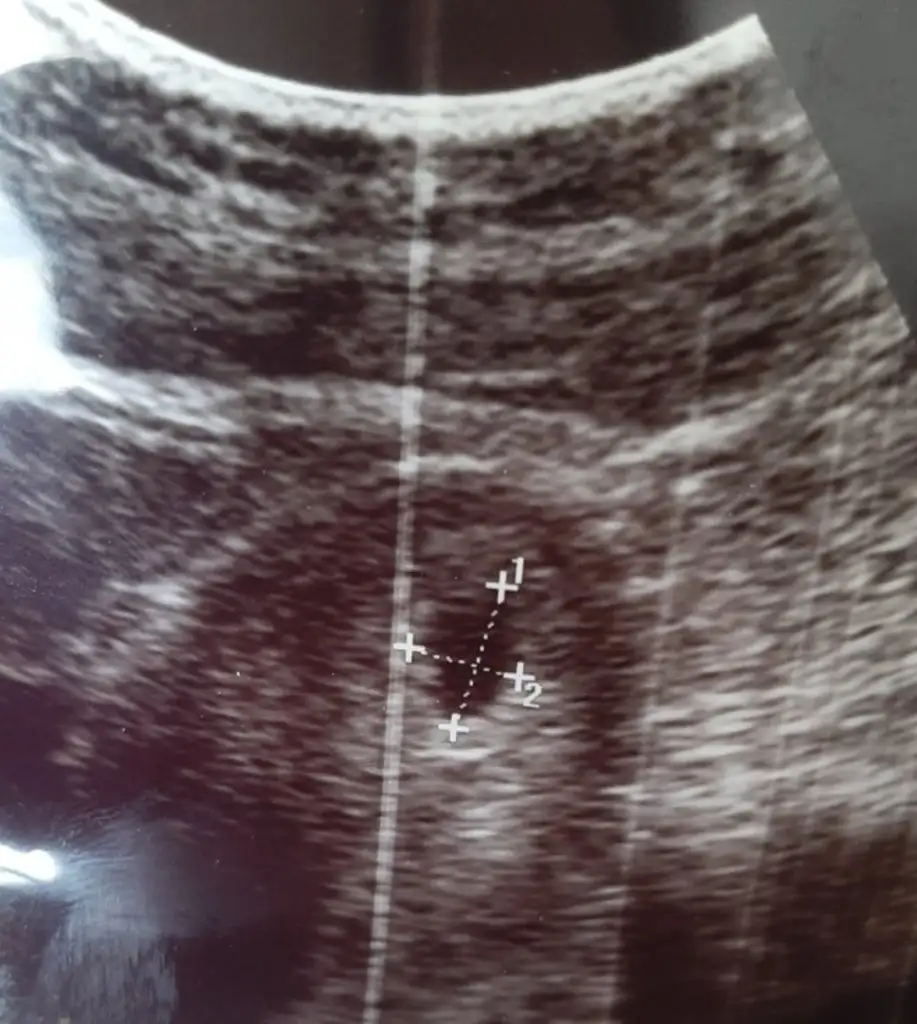

Videoda yakaladıgın fotoğrafın birinde bi cıkıntı var canım altta örnegini attım o cıkıntı düz geliyorsa kız diyolar seninde kız gibi benim bebeğimde de var doktor kız gibi ama yanılabilirim kesin olarak 18 subatta söylüycem dedi. Randevu günlerimiz aynı bende zor sabrediyorum suan

Bana da bakabilir misin lütfen 5+4 erken belki ama merakRamziye gore erkek canım ama ilerleyen haftalarda netlesr